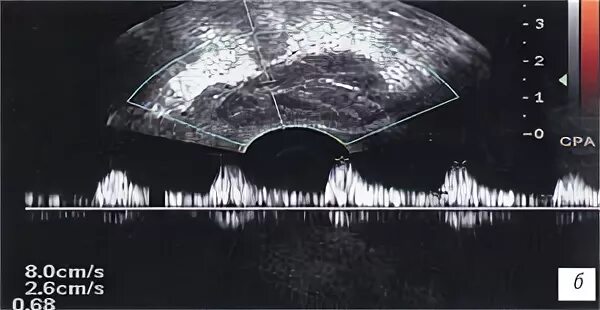

Простатит везикулит